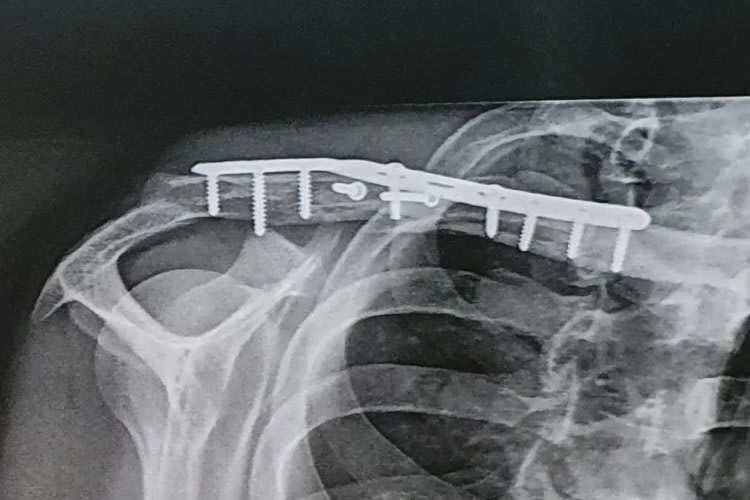

Beim Superbike-Meeting in Misano zog sich Chris Ponsson bei einem Sturz im ersten Lauf einen komplexen Schlüsselbeinbruch zu. Röntgenbilder belegen den desaströsen Zustand der Knochen, die Operation war schwierig.

Mit einem mehrfachen Schlüsselbeinbruch war das vierte Saisonmeeting für den Franzosen vorzeitig beendet, doch er muss auch um seine Teilnahme am Meeting in Donington Park am 16./17. Juli bangen. Denn die zur Fixierung des Knochens erforderliche Operation war aufwendig. "Es war kein einfacher Schlüsselbeinbruch", sagte der nur scheinbar gut gelaunte Ponsson. "Bevor die Rekonstruktion mit einer Platte und zehn Schrauben möglich war, mussten Muskeln und Nerven durchtrennt werden, um die Knochenstücke wieder an die richtige Stelle zu platzieren. Ich arbeite jeden Tag mit meinem Physiotherapeuten, um in etwas mehr als zwei Wochen für das nächste Rennen in England so gut wie möglich wieder fit zu sein." Der 26-jährige Ponsson fährt seine zweite Saison mit der Yamaha R1. Den im letzten Drittel 2021 gezeigten Aufwärtstrend konnte er in diesem Jahr nicht fortsetzen und belegt mit 8 WM-Punkten den 22. WM-Rang.